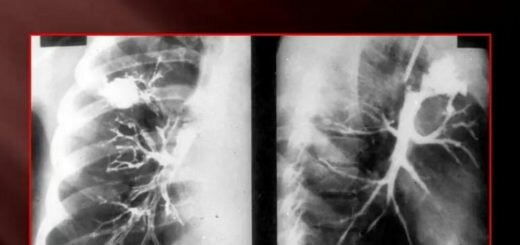

Все диагностические мероприятия в таком случае, базируются в первую очередь на сбор анамнеза заболевания. Проводится рентгенография лёгких, лабораторные исследования крови на бактериологический и серологический анализы, Мокрота для выявления примесей и определения цвета.